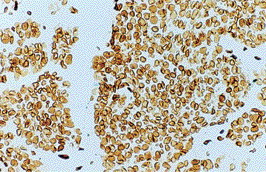

人乳腺癌:免疫组化染色Lamin B2采用NCL–LAM-B2。图示细胞核膜与所有细胞核内Lamin结构染色。冰冻切片(没有复染)。